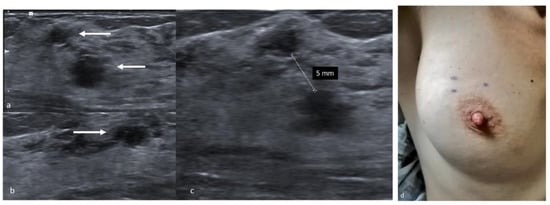

7. Radiofrequency Identification Tags